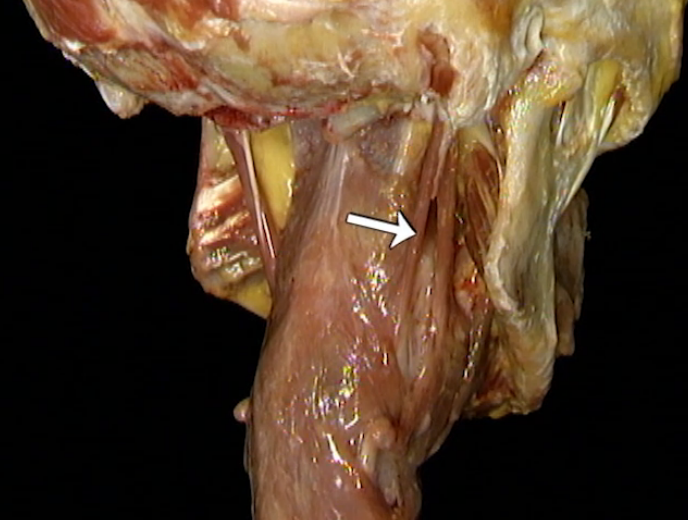

Which muscle is being indicated here?

Stylopharyngeus

Where does the stylopharyngeus muscle originate and insert?

Styloid process

Pharynx, between the layers of the superior and middle constrictors

What is the nerve supply to the stylopharyngeus?

CN IX